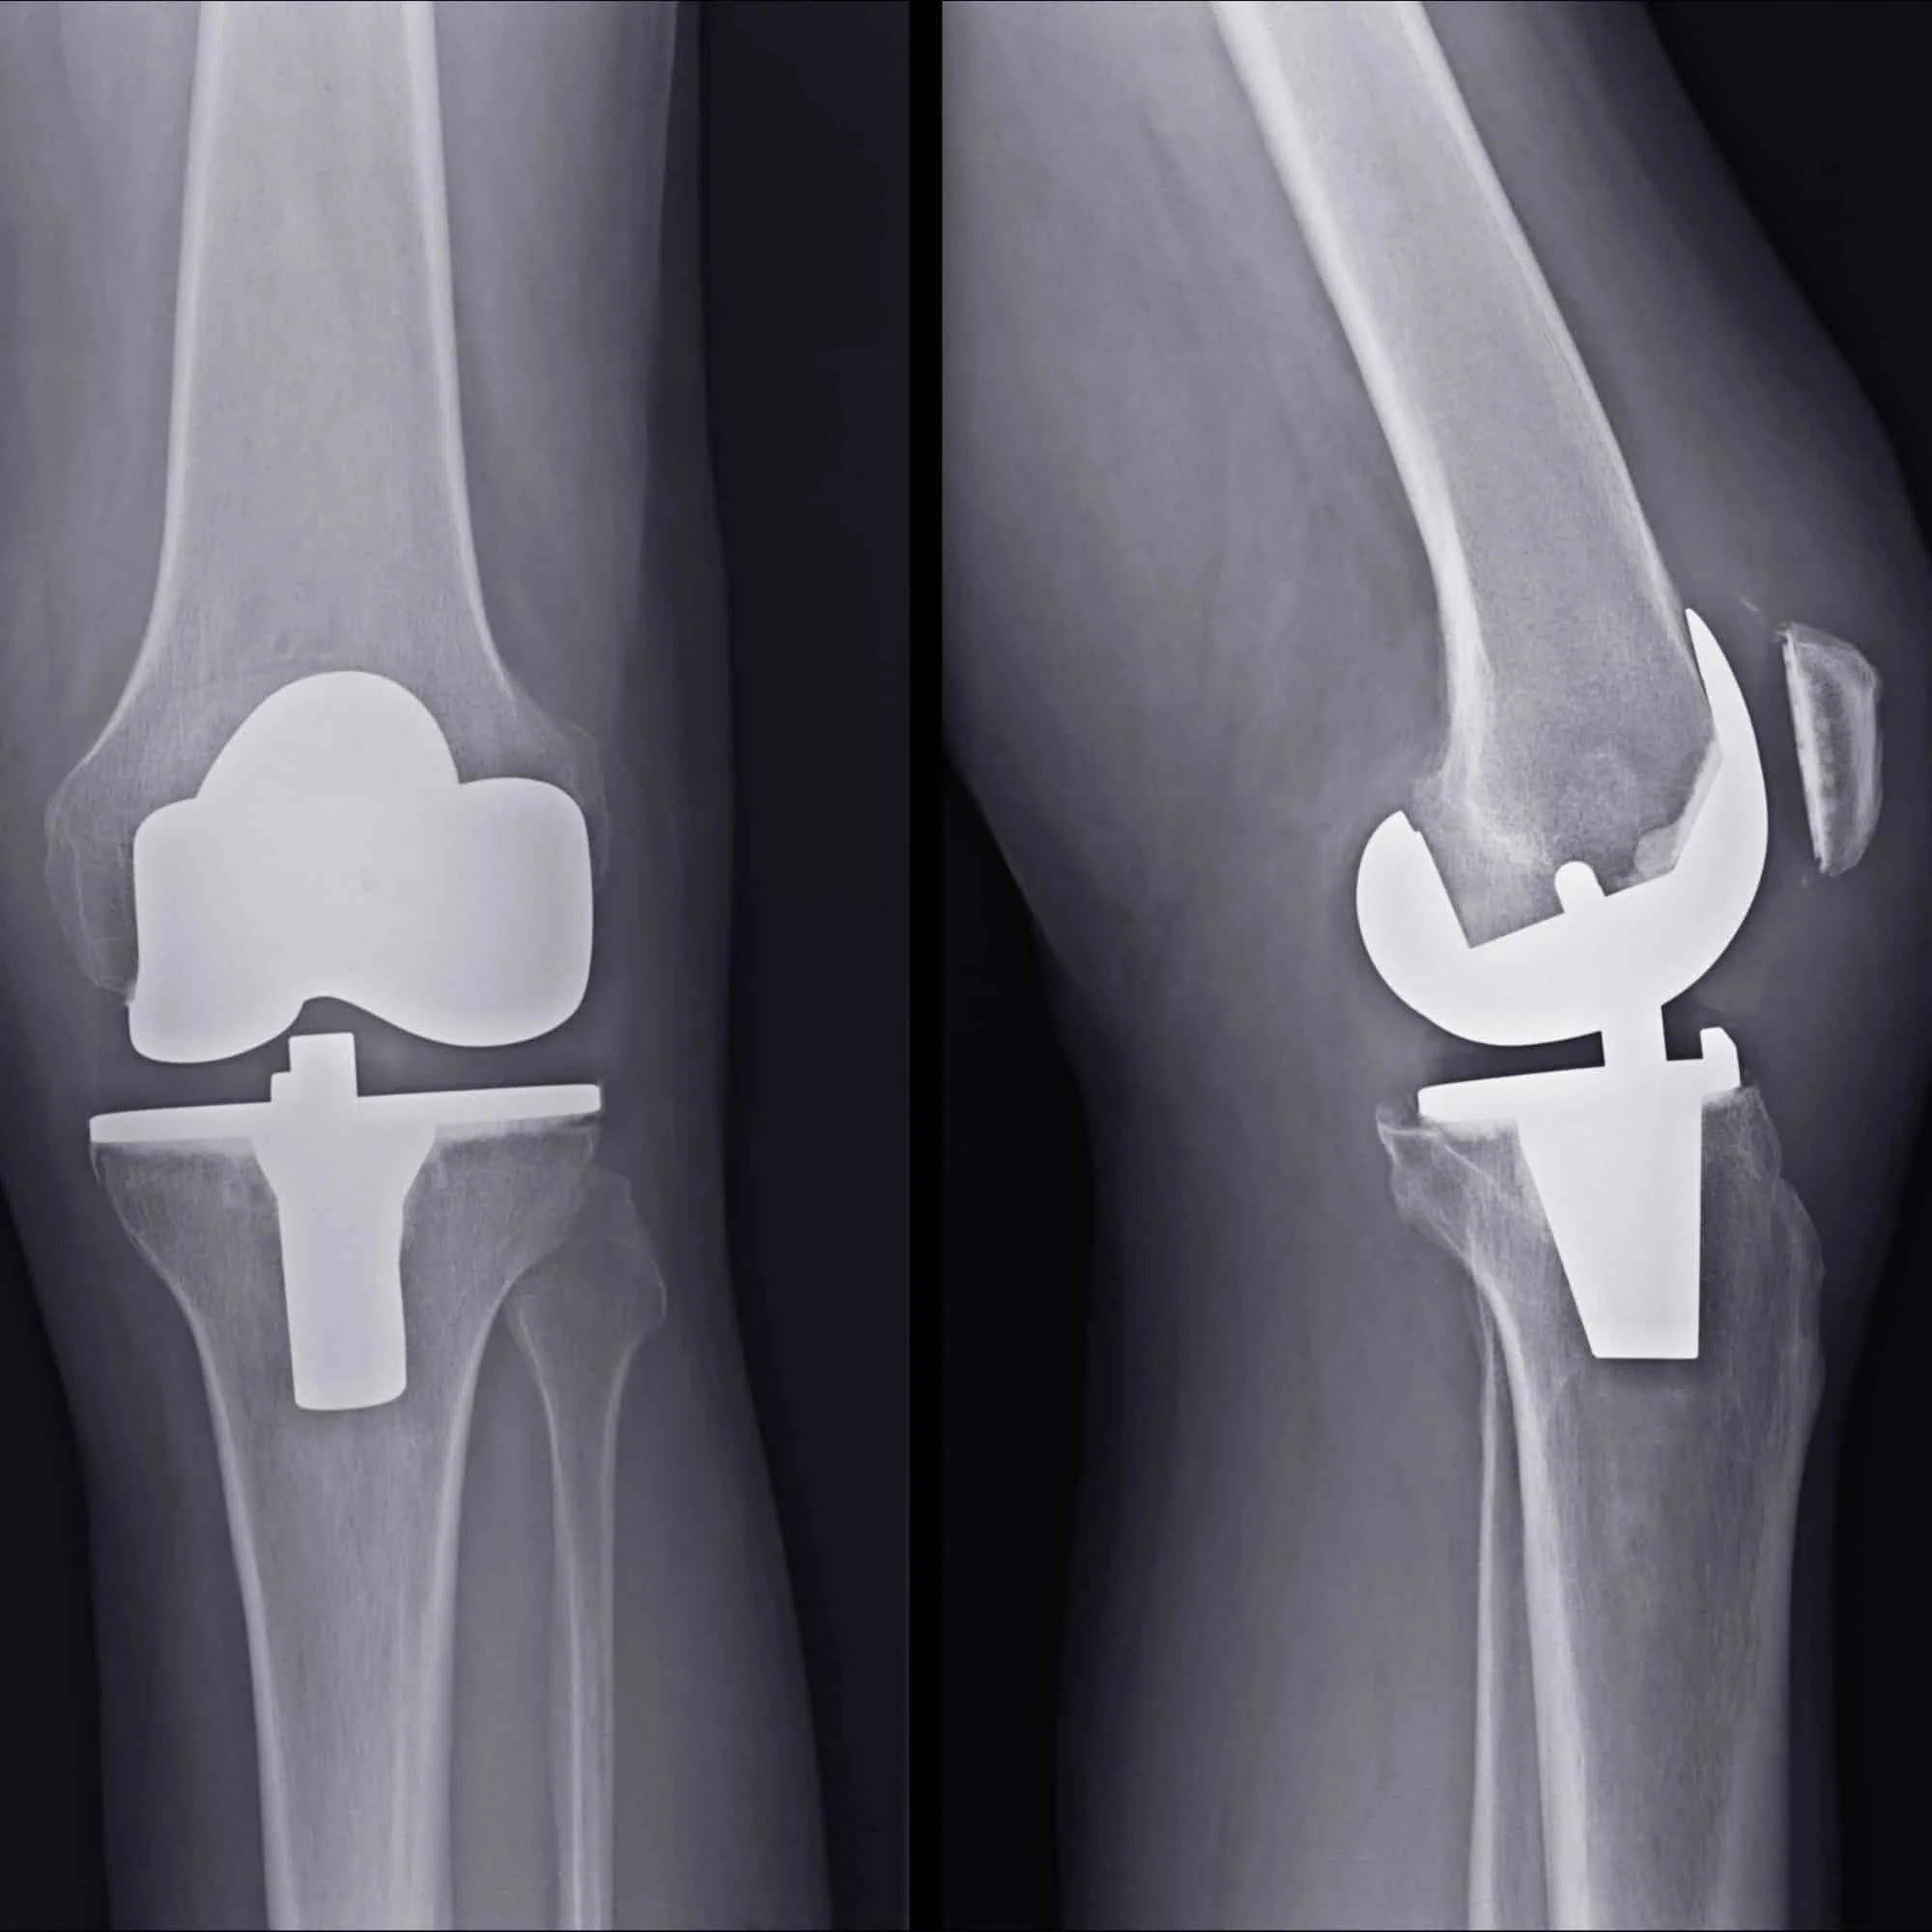

Physical Therapy After Total Knee Replacement: What the Latest Guidelines Mean for You

Curious what the experts say about recovering from a knee replacement? This research summary breaks down the latest Clinical Practice Guidelines on total knee arthroplasty rehabilitation: what works, what doesn’t, and what you can expect in the weeks and months after surgery.

Integrated Education Before and After Knee Replacement: A Better Path to Recovery?

A 2022 clinical study found that structured education before and after TKA helped reduce pain and anxiety while improving recovery speed and mobility.

Recovering After Total Knee Replacement: How Digital Support May Help

Postoperative outcomes of a digital rehabilitation program after total knee arthroplasty: retrospective, observational feasibility study.